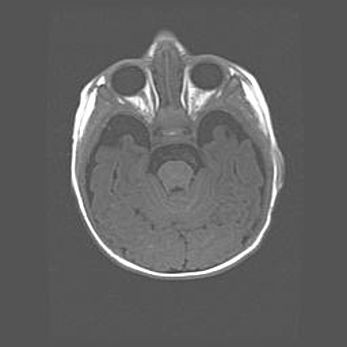

Множественные кисты обоих полушарий головного мозга, наибольшая из них в правой затылочной области. Ассиметричная атрофическая гидроцефалия.

Возраст: 7 месяцев

Вес: 5660 г

Пол: мужской

Окружность головы: 41,5 см

Срок гестации: 28-29 недель

Кисты головного мозга развиваются в результате многоочаговых некрозов вещества мозга и возникают вследствие перенесенной перинатальной инфекции, менингитов, энцефалитов, асфиксии, родовой травмы, расстройств мозгового кровообращения различного генеза. Образованию кист в веществе головного мозга плодов и новорожденных способствуют такие факторы, как высокое содержание в нем воды, недостаточная (или отсутствие) миелинизация и слабая астроглиальная реакция на повреждение.

Кисты могут сочетаться с гидроцефалией и другими поражениями головного мозга.